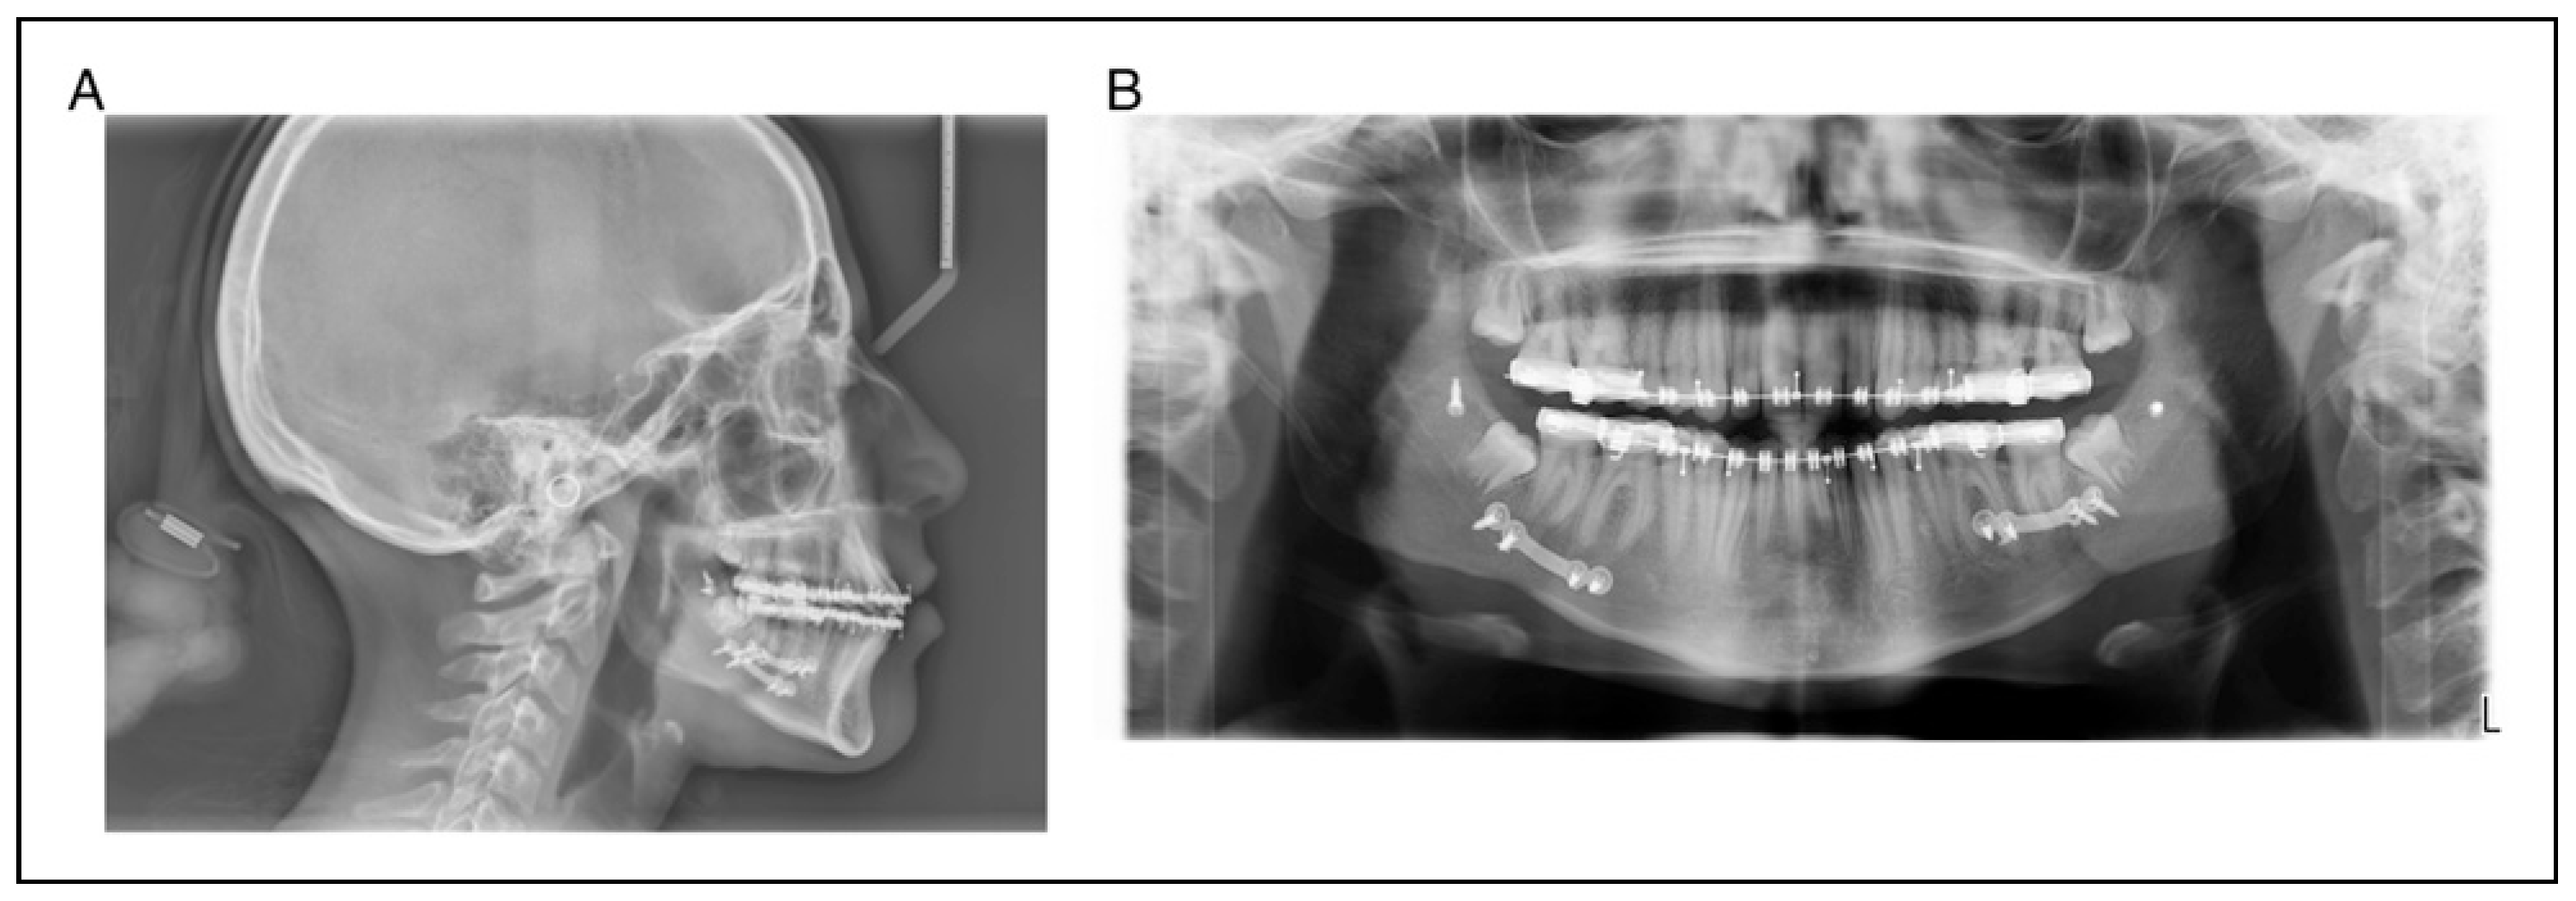

A 17-year-old woman presented for evaluation and treatment of mandibular hypoplasia (Figure 1A and 1B). Her medical history was significant for type I diabetes mellitus with an A1C of 8.1 one week prior to surgery. Her only prior surgery was tonsillectomy as a young child from which she recovered without issue. Her social history of negative for tobacco, alcohol, and drug use (smoking, vaping, use of tobacco of any kind). She received 1 g of cefazolin prior to incision. A bilateral sagittal split osteotomy (BSSO) was performed without intraoperative complication. Her lower third molars were not visualized during the surgery and were left in place. It was felt that removing them would lead to an unplanned fracture of the distal segment and that they would be removed at a later date. The mandible was fixed with a single 4-hole mono-cortical miniplate as well as 1 posterior bicortical screw bilaterally (Figure 2A and 2B). Her postoperative course was benign. She was admitted for 23-h observation during which time she received 2 doses of 3 g of Unasyn. She tolerated a clear liquid diet; postoperative radiographs were obtained (Figure 2A and 2B).

Figure 1. A, B Pre-op cephalometric and panoramic radiographs.